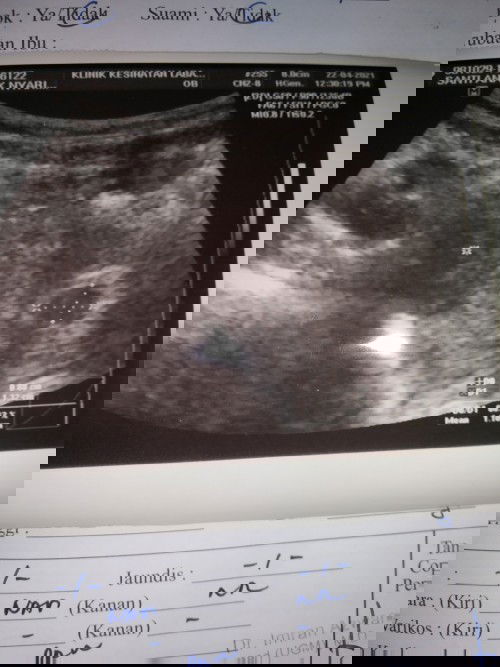

Kandungan kira2 5 ker 6 minggu..adakah normal nampak kantung saja..

normal ja dlu sya dlm lgkungan 5/6 week lgu la..x nmpk kntung n bby..doc sruh rfer dkt hos tkot luar rhim..aftr 3 week gtu la sya check balik bru ada..awai lg kot..dia ikut org..stgh dh nmpk stgh x nmpk lg..hihi..so jgn risau..in sha allah xdk apa.😊

normal sis, saya scan 7 minggu baru nampak janin tu pun masa scan ukuran baby 6weeks 5 day macam tu. so kalau nak scan nampak baby better sis scan aroun 8weeks plus. semoga sis dan baby baik baik je, amiin

sy pun mcm ni. scan 5minggu nampak kantung je,repeat scan 10minggu baru nampak baby dan heartbeat. tapi sis nak repeat scan dari 8minggu keatas pun dah boleh

normal Puan sebab terlalu awal. Selalu 8 weeks ke atas baru nampak kantung dan heartbeat. 😊 Moga ibu dan baby sihat selalu. 🥰

sy mula scan 6 minggu pon mcm ni nampak kantung je, dr suruh dtg scan balik lps 2 minggu baru nampak baby kt dlm